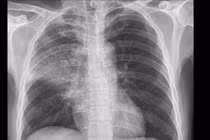

Bệnh nhân Đ.Đ.Th., 46 tuổi, xơ gan do rượu, nhiều lần xuất huyết tiêu hóa do giãn tĩnh mạch thực quản và phình vị. Trước đó, anh từng được nội soi thắt vòng cao-su và nút tắc búi giãn xuyên gan (ATO). Lần này, bệnh nhân nhập viện trong tình trạng xuất huyết tiêu hóa tái phát, cổ chướng nhiều, phù hai chi dưới và đau tức vùng bụng.

TIPS là kỹ thuật xâm lấn tối thiểu chỉ định cho bệnh nhân xơ gan mất bù.

Sau hội chẩn liên chuyên khoa Nội Tiêu hóa, Ngoại Tổng hợp và Điện quang can thiệp, bệnh nhân được chỉ định thực hiện can thiệp TIPS. Đây là thủ thuật được Bộ Y tế xếp loại phẫu thuật loại I, đòi hỏi trình độ kỹ thuật và trang thiết bị cao.

Ê-kíp do Thạc sĩ, bác sĩ Nguyễn Duy Thịnh, Trưởng Đơn nguyên Can thiệp mạch, trực tiếp thực hiện. Ca can thiệp kéo dài hơn ba giờ, đòi hỏi sự chính xác tuyệt đối khi bác sĩ phải tạo được đường thông giữa tĩnh mạch cửa và tĩnh mạch gan - hai cấu trúc chỉ cách nhau vài milimét trong gan xơ cứng.

Sau khi stent được đặt thành công, dòng lưu thông giữa tĩnh mạch cửa và tĩnh mạch chủ được tái lập, áp lực tĩnh mạch cửa giảm rõ rệt. Bệnh nhân tỉnh táo, sức khỏe ổn định và đang được theo dõi tại Khoa Hồi sức tích cực.